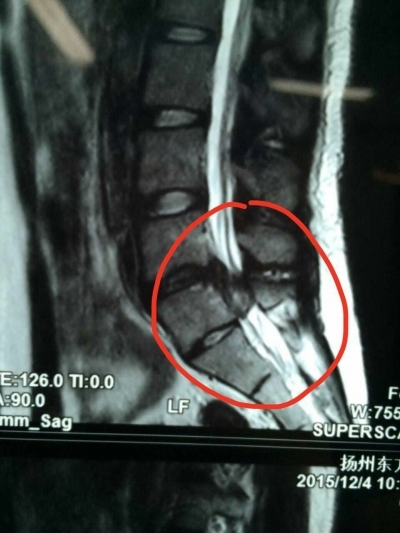

矢状位上见髓核游离至椎间隙上方,增大了手术难度.